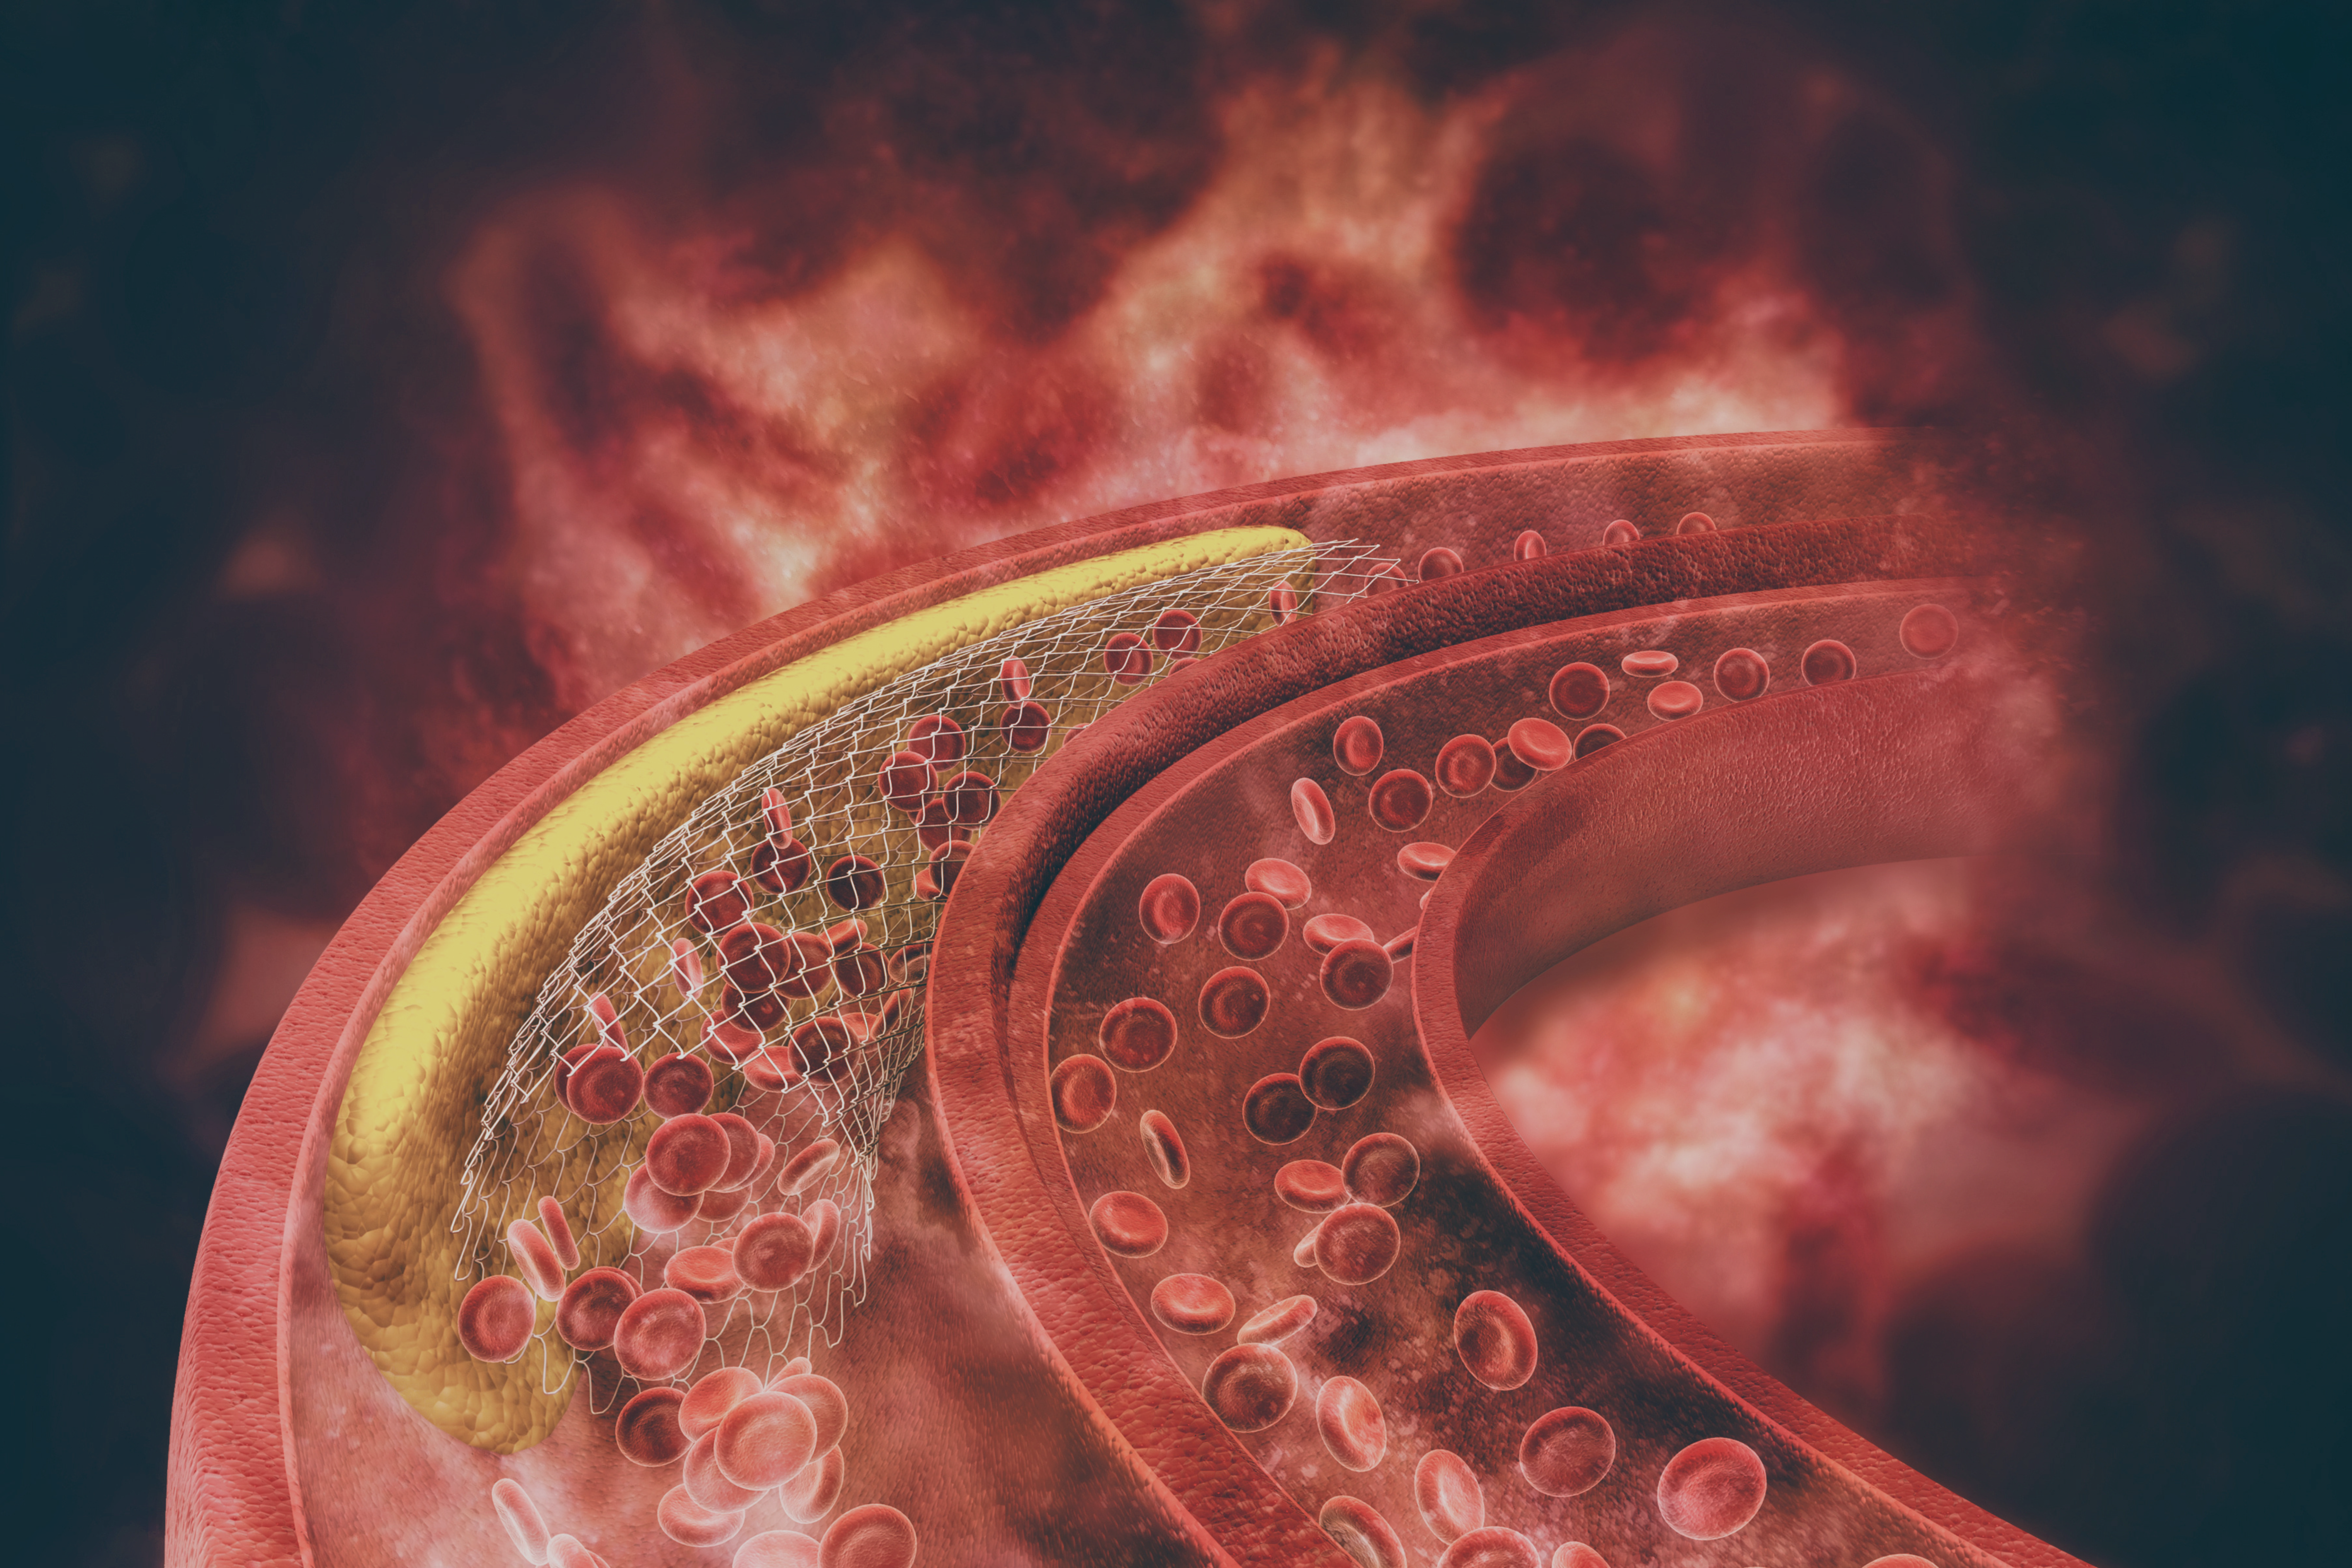

TC (TAC) coronarica 3D

Grazie alla nostra tecnologia avanzata, siamo in grado di effettuare esami TC (TAC) coronarici in 3D, fondamentali per valutare lo stato delle arterie coronarie e individuare eventuali patologie cardiovascolari.